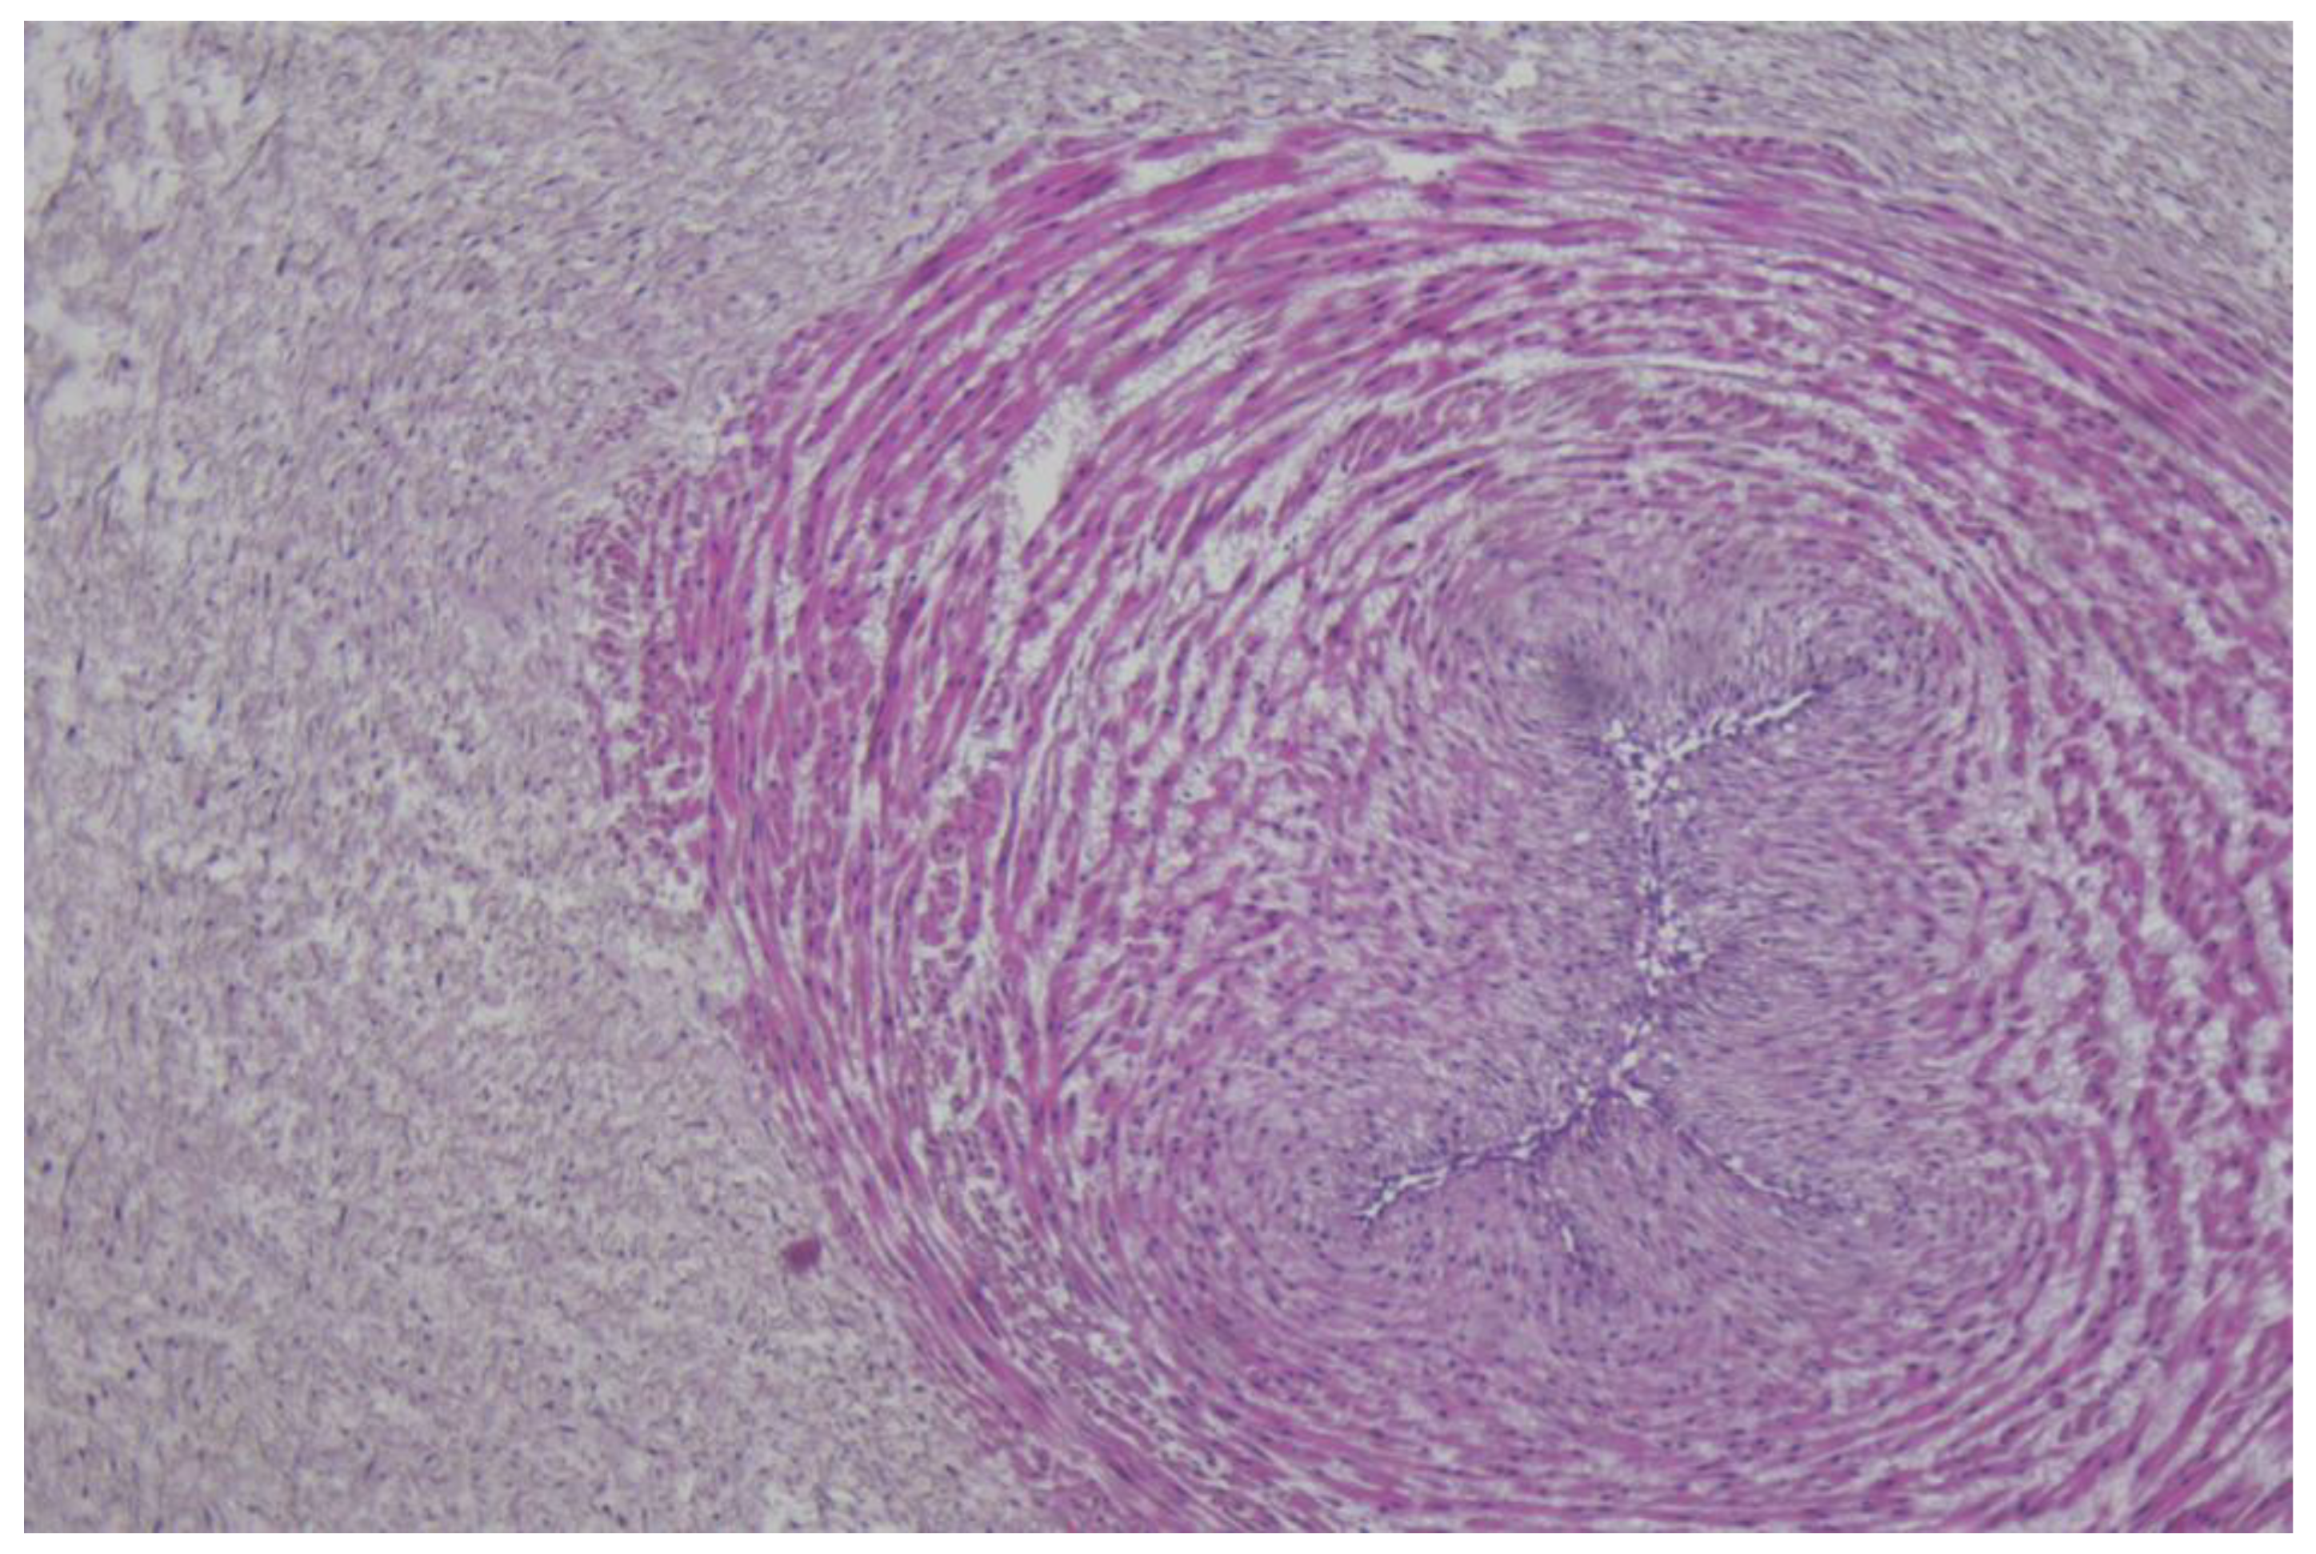

The immunohistochemistry analysis of the umbilical cord, amniotic membranes, and placental fragments from pregnant patients with COVID-19 failed to demonstrate positivity for the following markers: CD19, CD3, CD4, CD8, and CD56. These antibodies were used in order to find the inflammatory cells in the analyzed tissues as follows: CD19 for B cells, CD3 for T cells, CD4 for T helper cells, CD8 for cytotoxic T cells, and CD56 for NK cells. Tissue samples stained with hematoxylin and eosin, as well as immunohistochemical markings, are presented in Figure 1, Figure 2 and Figure 3.

Figure 1.

Selected microscopic aspects from placental sections: (A) Presence of intramural fibrin deposition and lack of inflammatory cells, H&E stain, ×100 magnification. (B–F) Negativity for the immune markings: (B) CD4, ×100 magnification, (C) CD8, ×200 magnification, (D) CD19, ×200 magnification, (E) CD3, ×200 magnification, (F) CD56, ×200 magnification.

Finally, our immunohistochemistry analysis of umbilical cords, amniotic membranes, and placental fragments retrieved in the third trimester of pregnancy failed to demonstrate positivity for CD19, CD3, CD4, CD8, and CD56 markers. In a recent study by Levitan et al., the authors evaluated 64 placentas using immunohistochemical staining for SARS-CoV-2 nucleocapsid protein, and found that none of the specimens were positive for this marker [52]. Another study that analyzed the immunohistochemical staining of placental specimens for various leukocytes revealed an increased CD68+ macrophage infiltration [53].

Resta et al. investigated the association between the symptoms’ severity and different placental histological characteristics using immunohistochemical investigations for CD4 + and CD8 + T lymphocytes, and CD68 + macrophages [26]. The authors did not observe significant differences between patients with mild or severe forms of COVID-19 and controls for CD4. CD8 expression was significantly higher in placentas from patients with severe forms compared with controls, while the CD68 expression was significantly different between the evaluated groups. Finally, Juttukonda et al. characterized the decidual immune response depending on the timing of infection during gestation, and demonstrated that for an infection acquired in the third trimester of pregnancy, decidual tissues presented significantly more macrophages (CD14+), NK cells (CD56+), and T cells (CD3+) [54]. For the infection acquired in the second trimester of pregnancy, only T cells (CD3+) were significantly more expressed in the evaluated placentas.

We hypothesize that a possible explanation for the lack of immunohistochemical positivity of the evaluated markers in the placenta, umbilical cord, and amniotic membranes could be represented by the fact that SARS-CoV-2 infection occurred in the third trimester of pregnancy for the patients enrolled in the study, and the timeframe from infection to birth was generally short for an intensive local immune response.